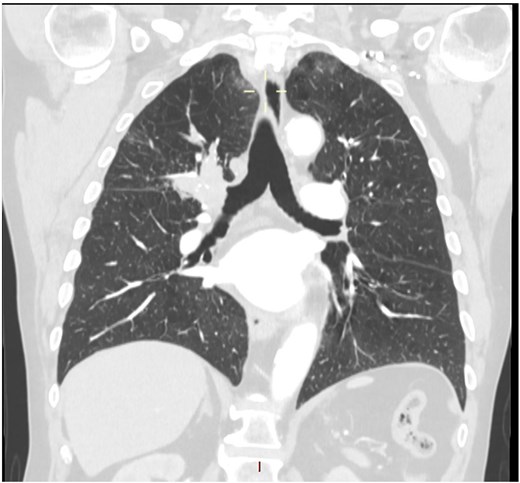

This 78-year-old man initially presented with a chest infection in October 2024, where a chest X-Ray (CXR) showed right upper lobe (RUL) consolidation accompanied by a pleural effusion (Fig. 1). He had no other symptoms, including haemoptysis, shortness of breath, fever, anorexia, or weight loss. A follow-up computed tomography (CT) chest 6 weeks later revealed a large endobronchial lesion in the right main bronchus, resulting in consolidation and partial collapse of the RUL (Figs 2 and 3). He went on to have a positron emission tomography (PET) scan (Fig. 4), CT head, bronchoscopy, and endobronchial ultrasound (EBUS). Imaging revealed a 3.8 cm lesion in the right upper lobe bronchus, which was mostly occluded. The biopsies showed evidence of a myoepithelial carcinoma, a rare pulmonary neoplasm.

CT scan (coronal section) showing a large endobronchial lesion within the right upper lobe bronchus causing distal collapse of the right upper lobe.